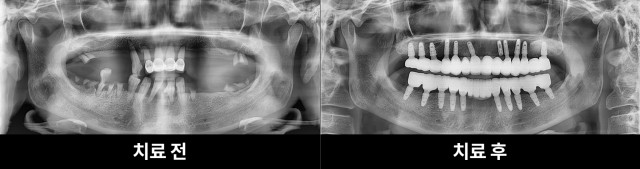

[211118 ~ 221121] 김**님 치료과정

2022-12-19